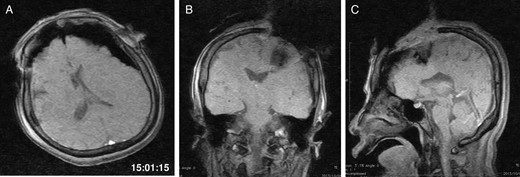

General anaesthesia was induced. Following left frontal craniotomy and dural incision, the first iMRI was performed (Fig. 1 ). One hundred fifty-eight minutes from induction, the patient regained consciousness after all anaesthetics were ceased. Tumour resection was performed with free conversation. However, after 143 min of surgery under the awake condition, the patient came to complain of excessive sleepiness though she could respond to verbal commands. Electrocorticogram (ECoG) did not detect after-discharge. The tumour was successfully removed en bloc fashion. Progressive brain swelling was not observed. The second iMRI was commenced 182 min into the awake phase (Fig. 2). Thirteen minutes from the beginning of the second iMRI scanning, the patient did not respond to noxious stimuli. When the patient was removed from the gantry, she was unconscious and had stopped spontaneous breathing. Her pupils were isocoria and did not dilate. Neither epileptic seizure nor anaphylactic reaction occurred. The peripheral oxygen saturation was not measurable, but cardiac instability or signs of vomiting were not observed. We decided to discontinue the operation under the awake status. No electrolyte imbalance or hypoglycaemia was observed. Subsequently performed iMRI identified a thin subdural haematoma in the contralateral side (Fig. 3). The fourth iMRI confirmed that most of the haematoma was evacuated following right frontal craniotomy.

The third intraoperative magnetic resonance images after intubation, axial (A), coronal (B) and sagittal (C) T1-weighted scout images show acute right-sided subdural hematoma (arrows), contralateral to the site of the craniotomy. The time of scan is superimposed.